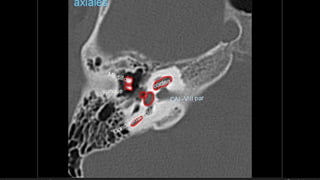

Hipoacusia

 Conductiva  26-57% -- longitudinal – lesión osicular, MT, Hemotimpano

 Dislocacion incudoestapedial  57-80%

 Dislocacion incudomaleolar 51%

 Fractura estapedio  30%

Hipoacusia  Conductiva 26-57% -- longitudinal – lesión osicular, MT, Hemotimpano  Sensorial  14-23% -- transversa -- OCV  Mixta  20-55%  Dislocacion incudoestapedial  57-80%  Dislocacion incudomaleolar 51%  Fractura estapedio  30%  Fractura martillo  8%